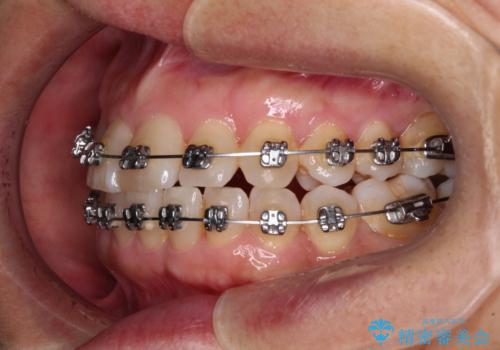

- メタルブラケット

- 1年8ヶ月

- 骨格的な咬み合わせのズレ、前歯のデコボコとクロスバイトを気にして来院された患者様です。

奥歯の噛みにくさが顕著なためマウスピースではなく、ワイヤー装置による矯正治療を行うこととしました。

下顎の正中を歯1本分ずらした位置とすることで、外見上の骨格的なずれをカバーするように計画しました。

クロスバイトを改善したことで、前歯の負担が軽減し、安定して噛めるようになりました。